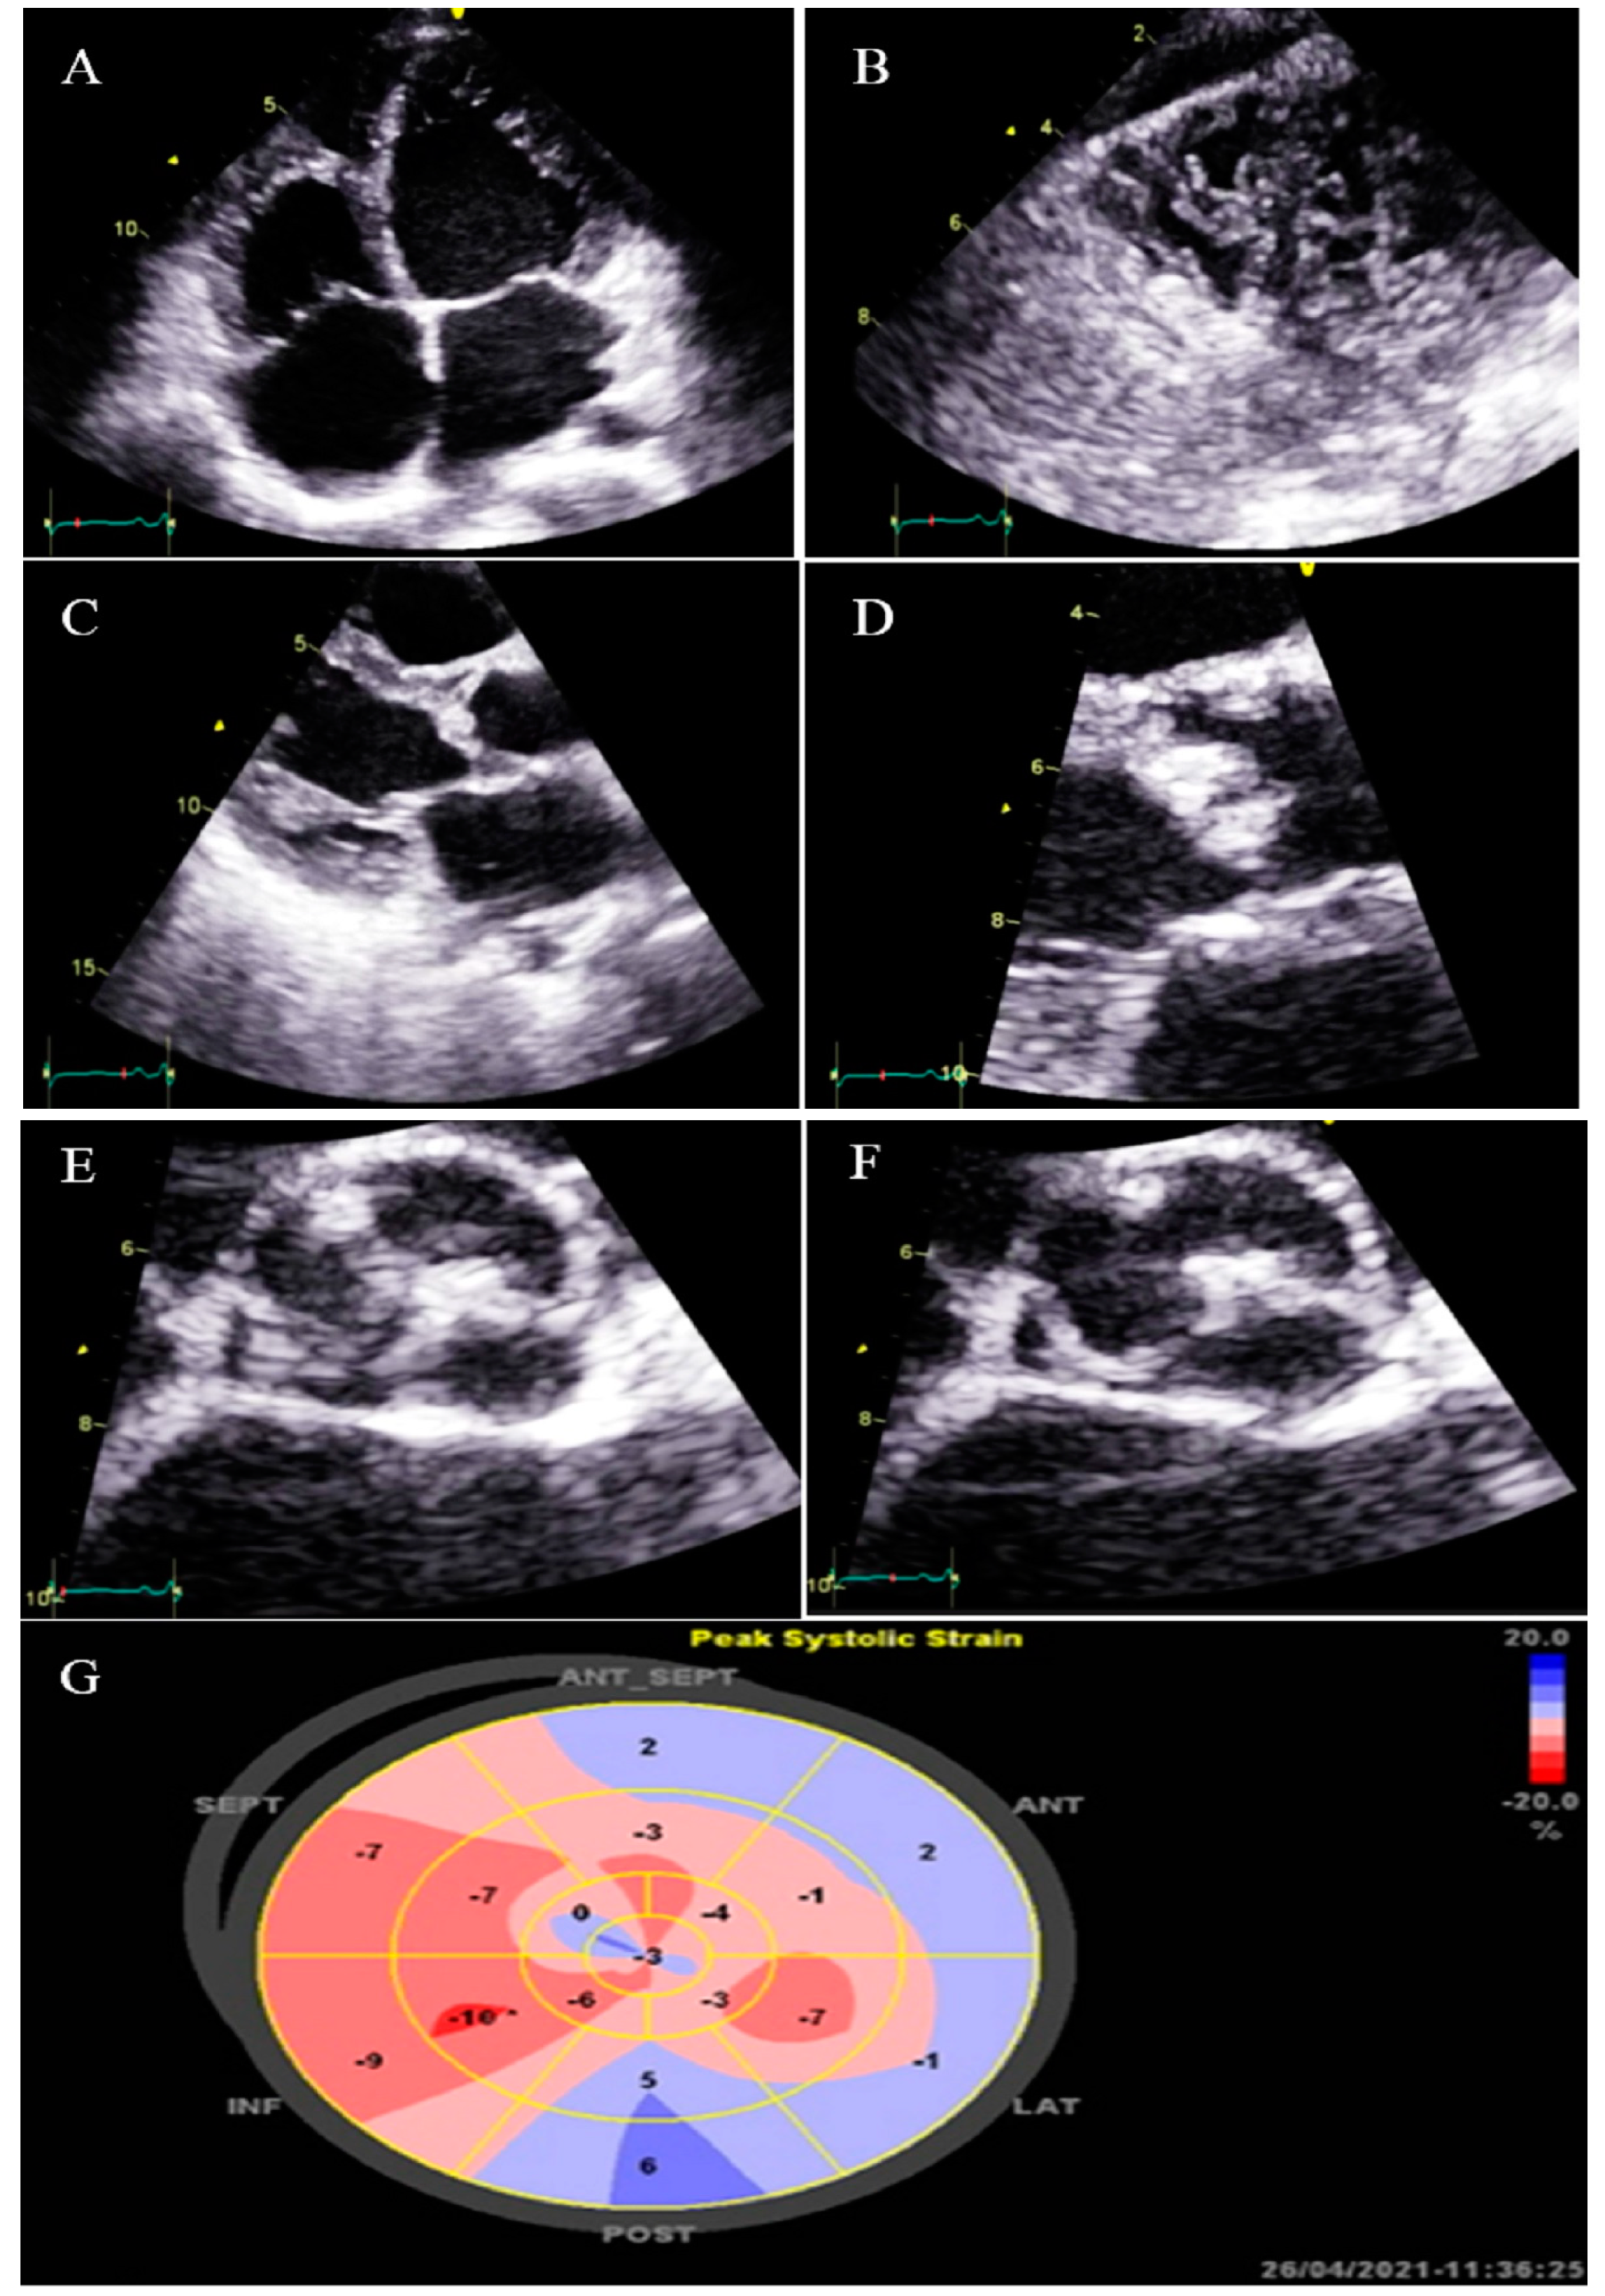

2.11. Case #11. NCLV, BAV, and Old Myocardial Infarction

| 11 | F | 62 | Echocardiography before diagnostic angiography | Old MI, DM, HLP | NCLV, LVEF = 34% | BAV | − | − | Indicated for CABG according to the result of coronary angiography, she refused and left the hospital | Did not refer again to our center |